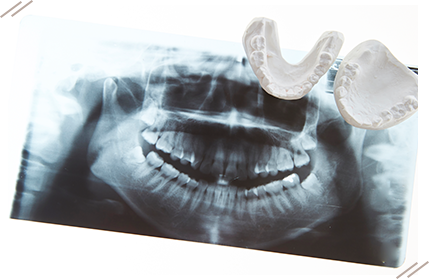

レントゲン撮影、口腔内写真、歯型取り、3Dスキャナーなどを使い、顎や歯の状態を詳細に確認します。その後、診断結果に基づいて具体的な治療方針を決定します。